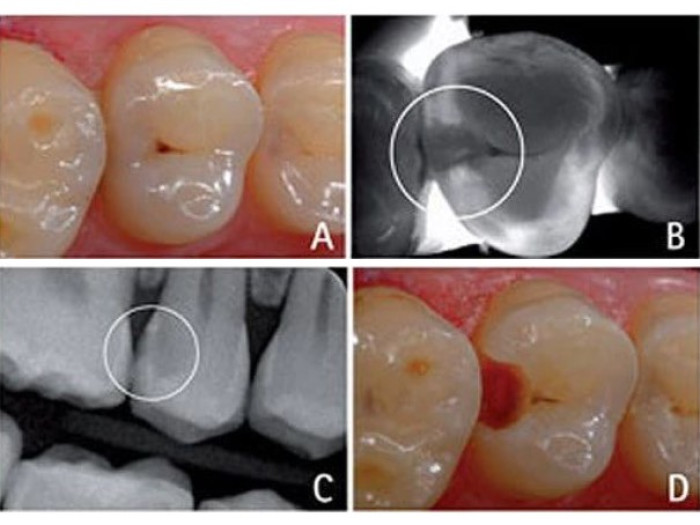

В данном исследовании представлен случай окклюзионно расположенного кариозного очага. Фиссуры на окклюзионной поверхности предрасположены к появлению кариеса в связи с ограниченными возможностями гигиены.

Соответственно, в профилактических целях фиссуры часто герметизируют. В данном случае классическая диагностика кариеса затруднена (А). При исследовании DIAGNOcam точно определяются очаги кариозных затемнений (см. круг B), которые были обнаружены и на рентгеновском снимке.